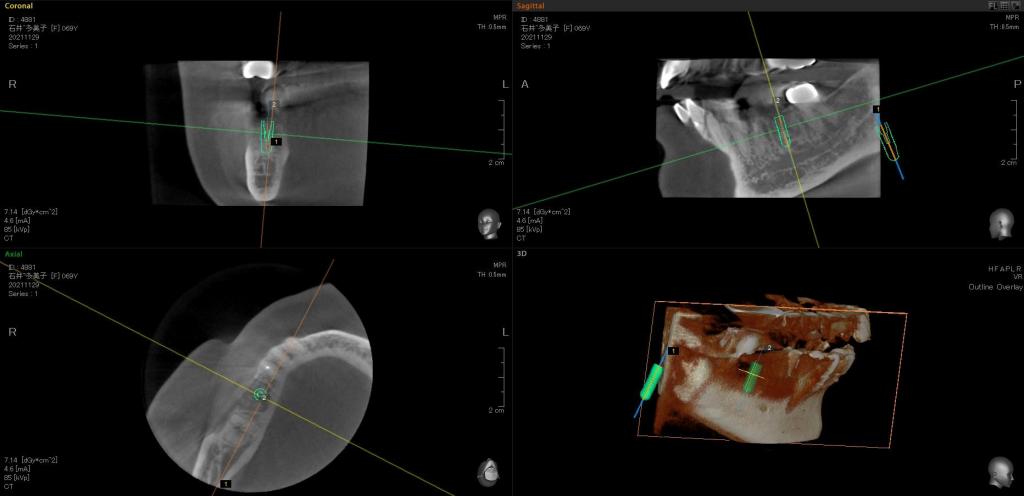

治療中写真

- 抜歯して骨を作る処置を行い、3ヶ月ほど経過後CTを撮影し、インプラントを行いました。